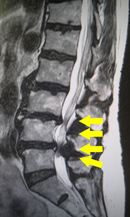

せぼねの変形や椎間板の傷み具合、不安定性の有無、脊柱管の狭さ、またせぼね全体のバランスなどを見るためにX線検査やCT検査、MRI検査などを行います。進行例では脊柱管の狭さをより詳しく評価するために入院して脊髄造影検査や、同時にどの神経が痛みの原因となっているかを明らかにするために神経の枝に直接麻酔薬を注入する選択的神経根ブロックを行う場合があります。成人期では血管性の下肢の痛みがないか評価するために両手足の血圧を測ったり、骨粗鬆症の有無を評価するために骨密度検査を行うこともあります。

せぼねの変形や椎間板の傷み具合、すべりや不安定性の程度、脊柱管の狭さ、またせぼね全体のバランスなどを見るためにX線検査やCT検査、MRI検査などを行います。進行例では脊柱管の狭さをより詳しく評価するために入院して脊髄造影検査や、同時にどの神経が痛みの原因となっているかを明らかにするために神経の枝に直接麻酔薬を注入する選択的神経根ブロックを行う場合があります。成人期では血管性の下肢の痛みがないか評価するために両手足の血圧を測ったり、骨粗鬆症の有無を評価するために骨密度検査を行うこともあります。

せぼねの変形や椎間板の傷み具合、すべりや不安定性の有無、脊柱管の狭さ、またせぼね全体のバランスなどを見るためにX線検査やCT検査、MRI検査などを行います。進行例では脊柱管の狭さをより詳しく評価するために入院して脊髄造影検査や、同時にどの神経が痛みの原因となっているかを明らかにするために神経の枝に直接麻酔薬を注入する選択的神経根ブロックを行う場合があります。成人期では血管性の下肢の痛みがないか評価するために両手足の血圧を測ったり、骨粗鬆症の有無を評価するために骨密度検査を行うこともあります。